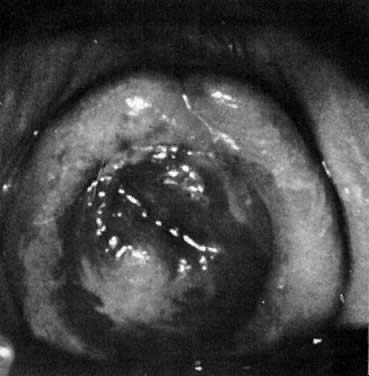

Urethral caruncles present as localized, red, friable lesions at the urethral meatus (Fig. 4, Fig. 5). They are generally seen in the postmenopausal woman and are thought to result from a localized area of prolapse of the urethral mucosa with secondary inflammatory changes. They can be confused with acute circumferential prolapse of the urethral mucosa, a condition usually seen in young girls. Urethral carcinoma must be excluded in patients with larger urethral caruncles. There may be pain, dysuria, and bleeding. Small asymptomatic urethral caruncles may not require any treatment. Larger or symptomatic lesions can be treated by topical application of estrogen. To establish the diagnosis, small biopsies may be performed under local anesthesia. Large or persistent lesions may require excision and reapproximation with fine absorbable suture.

Fig. 4. Urethral caruncle.(Courtesy of Dr. J. Merrill)